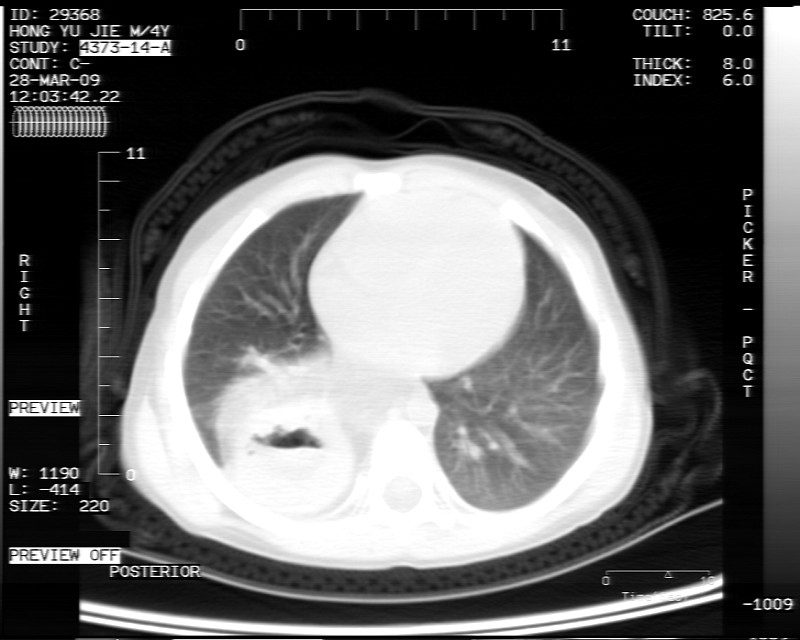

标题: PED1814:胸片体检发现右下肺病变。

男性,3岁,斜疝术前常规检查胸片体检发现右下肺病变。咳嗽,无发烧。

内有气体,液平面,考虑食管裂孔疝可能性大。建议食道钡透。

有液气平面,前部肺纹理聚集(受压改变),周围肺野及相邻胸膜清晰,支持膈疝,可吞服造影剂看一下。

考虑膈疝(右侧胸腹膜裂孔疝?)。